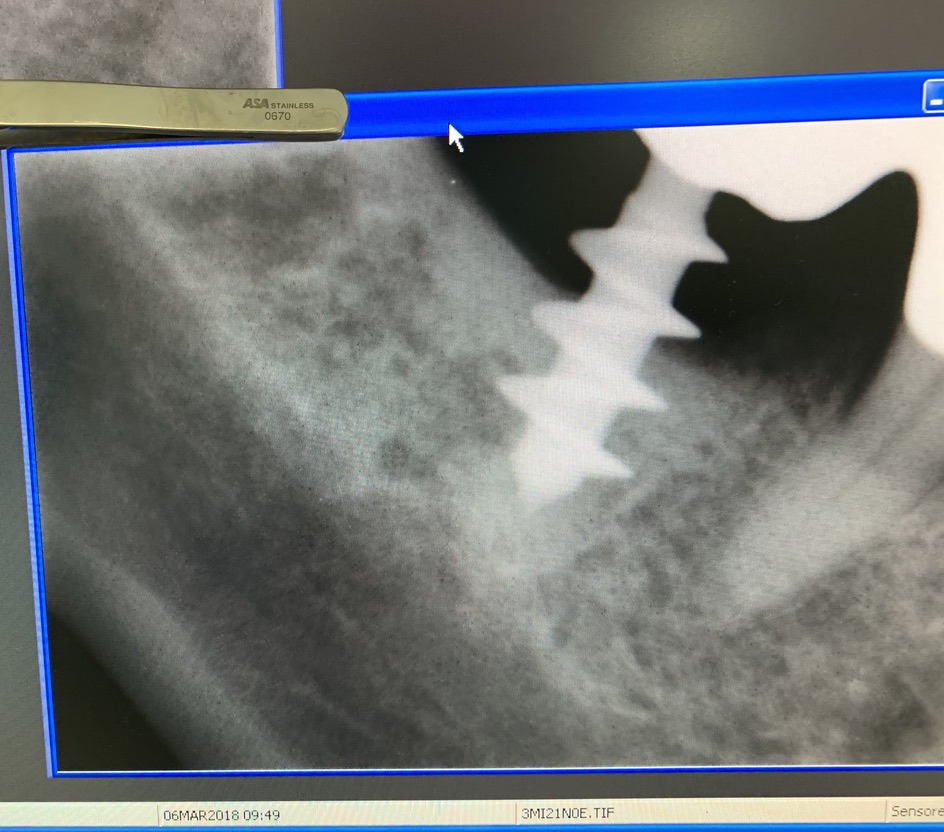

Forma originale dell’impianto di Tramonte. Diametro 5 mm a 3 spire. Gambo diam. 2,1 mm. Collo diam.2 mm x 5 mm di lunghezza. Titanio di grado 2. Il grado 2 consentiva al bisogno di piegare il collo dell’impianto per migliorare il parallelismo. Si tratta di un impianto postestrattivo immediato. Perciò nella stessa seduta estrazione, alesatura maschiatura ed inserimento dell’impianto. Subito seguiti da monconizzazione e da confezione di corone provvisorie in occlusione leggera. Le radiografie fornite evidenziano la situazione a partire dal 2010. La emergenza del collo sottile favorisce la formazione di un manicotto di gengiva densa che protegge dalle periimplantiti. Le spire larghe irradiano lontano dal corpo impianto il carico occlusale favorendo la formazione di un osso più omogeneo.